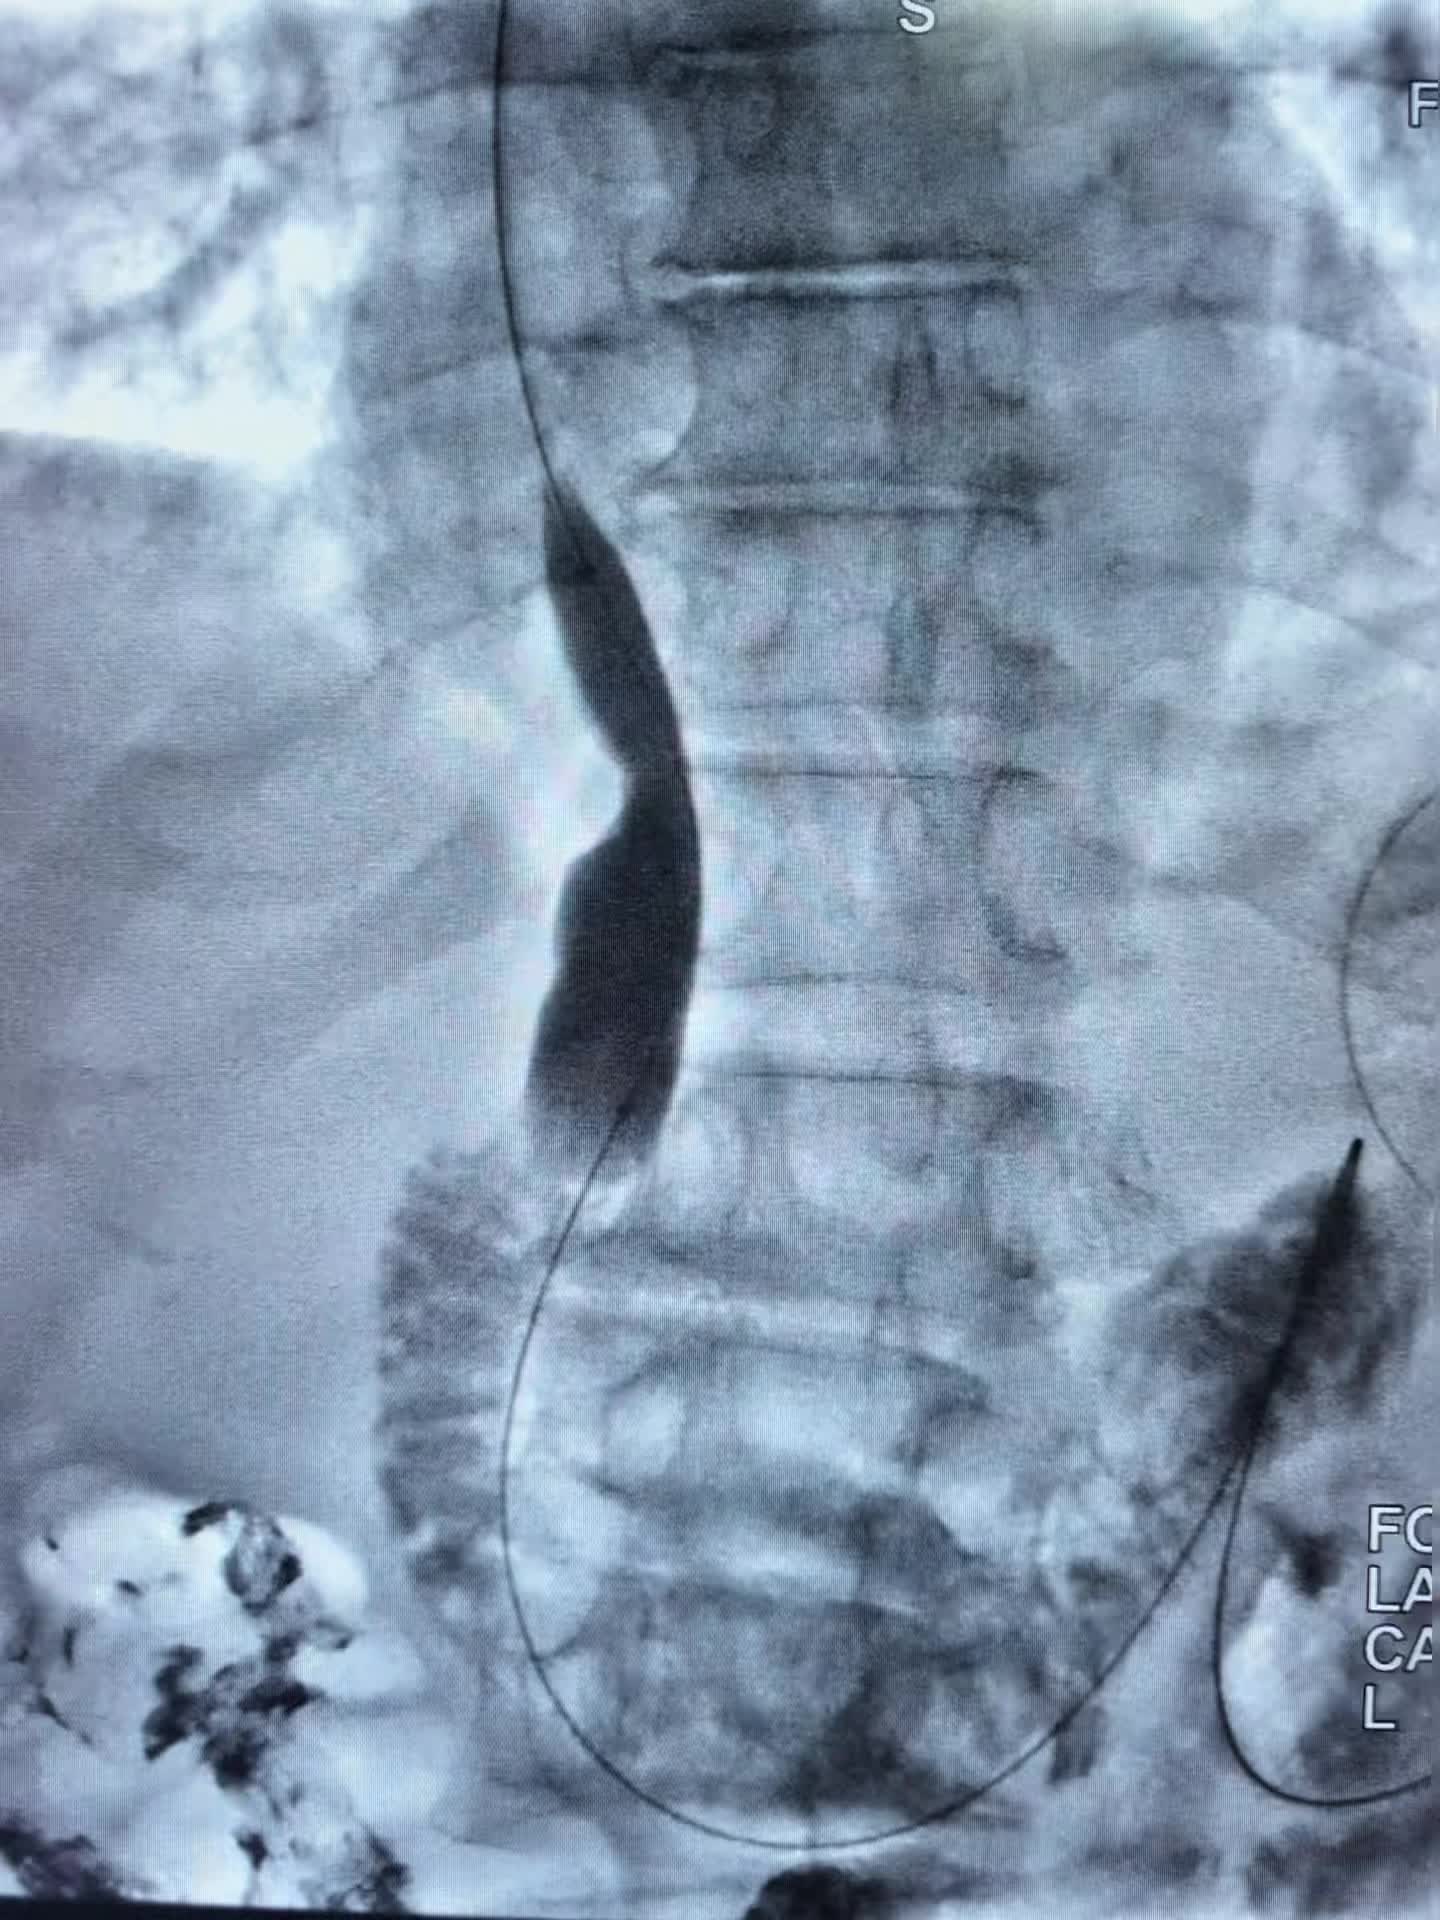

上午第一台78岁老年男性贲门癌患者,突发食管梗阻不能进食水,行球囊扩张,食管支架置入术,术即可恢复饮食。 第二台:食管癌术后3年再次进食哽咽,食管吻合口狭窄伴肠管膈肌处狭窄。单纯行球囊扩张术,术后即可恢复正常饮食。